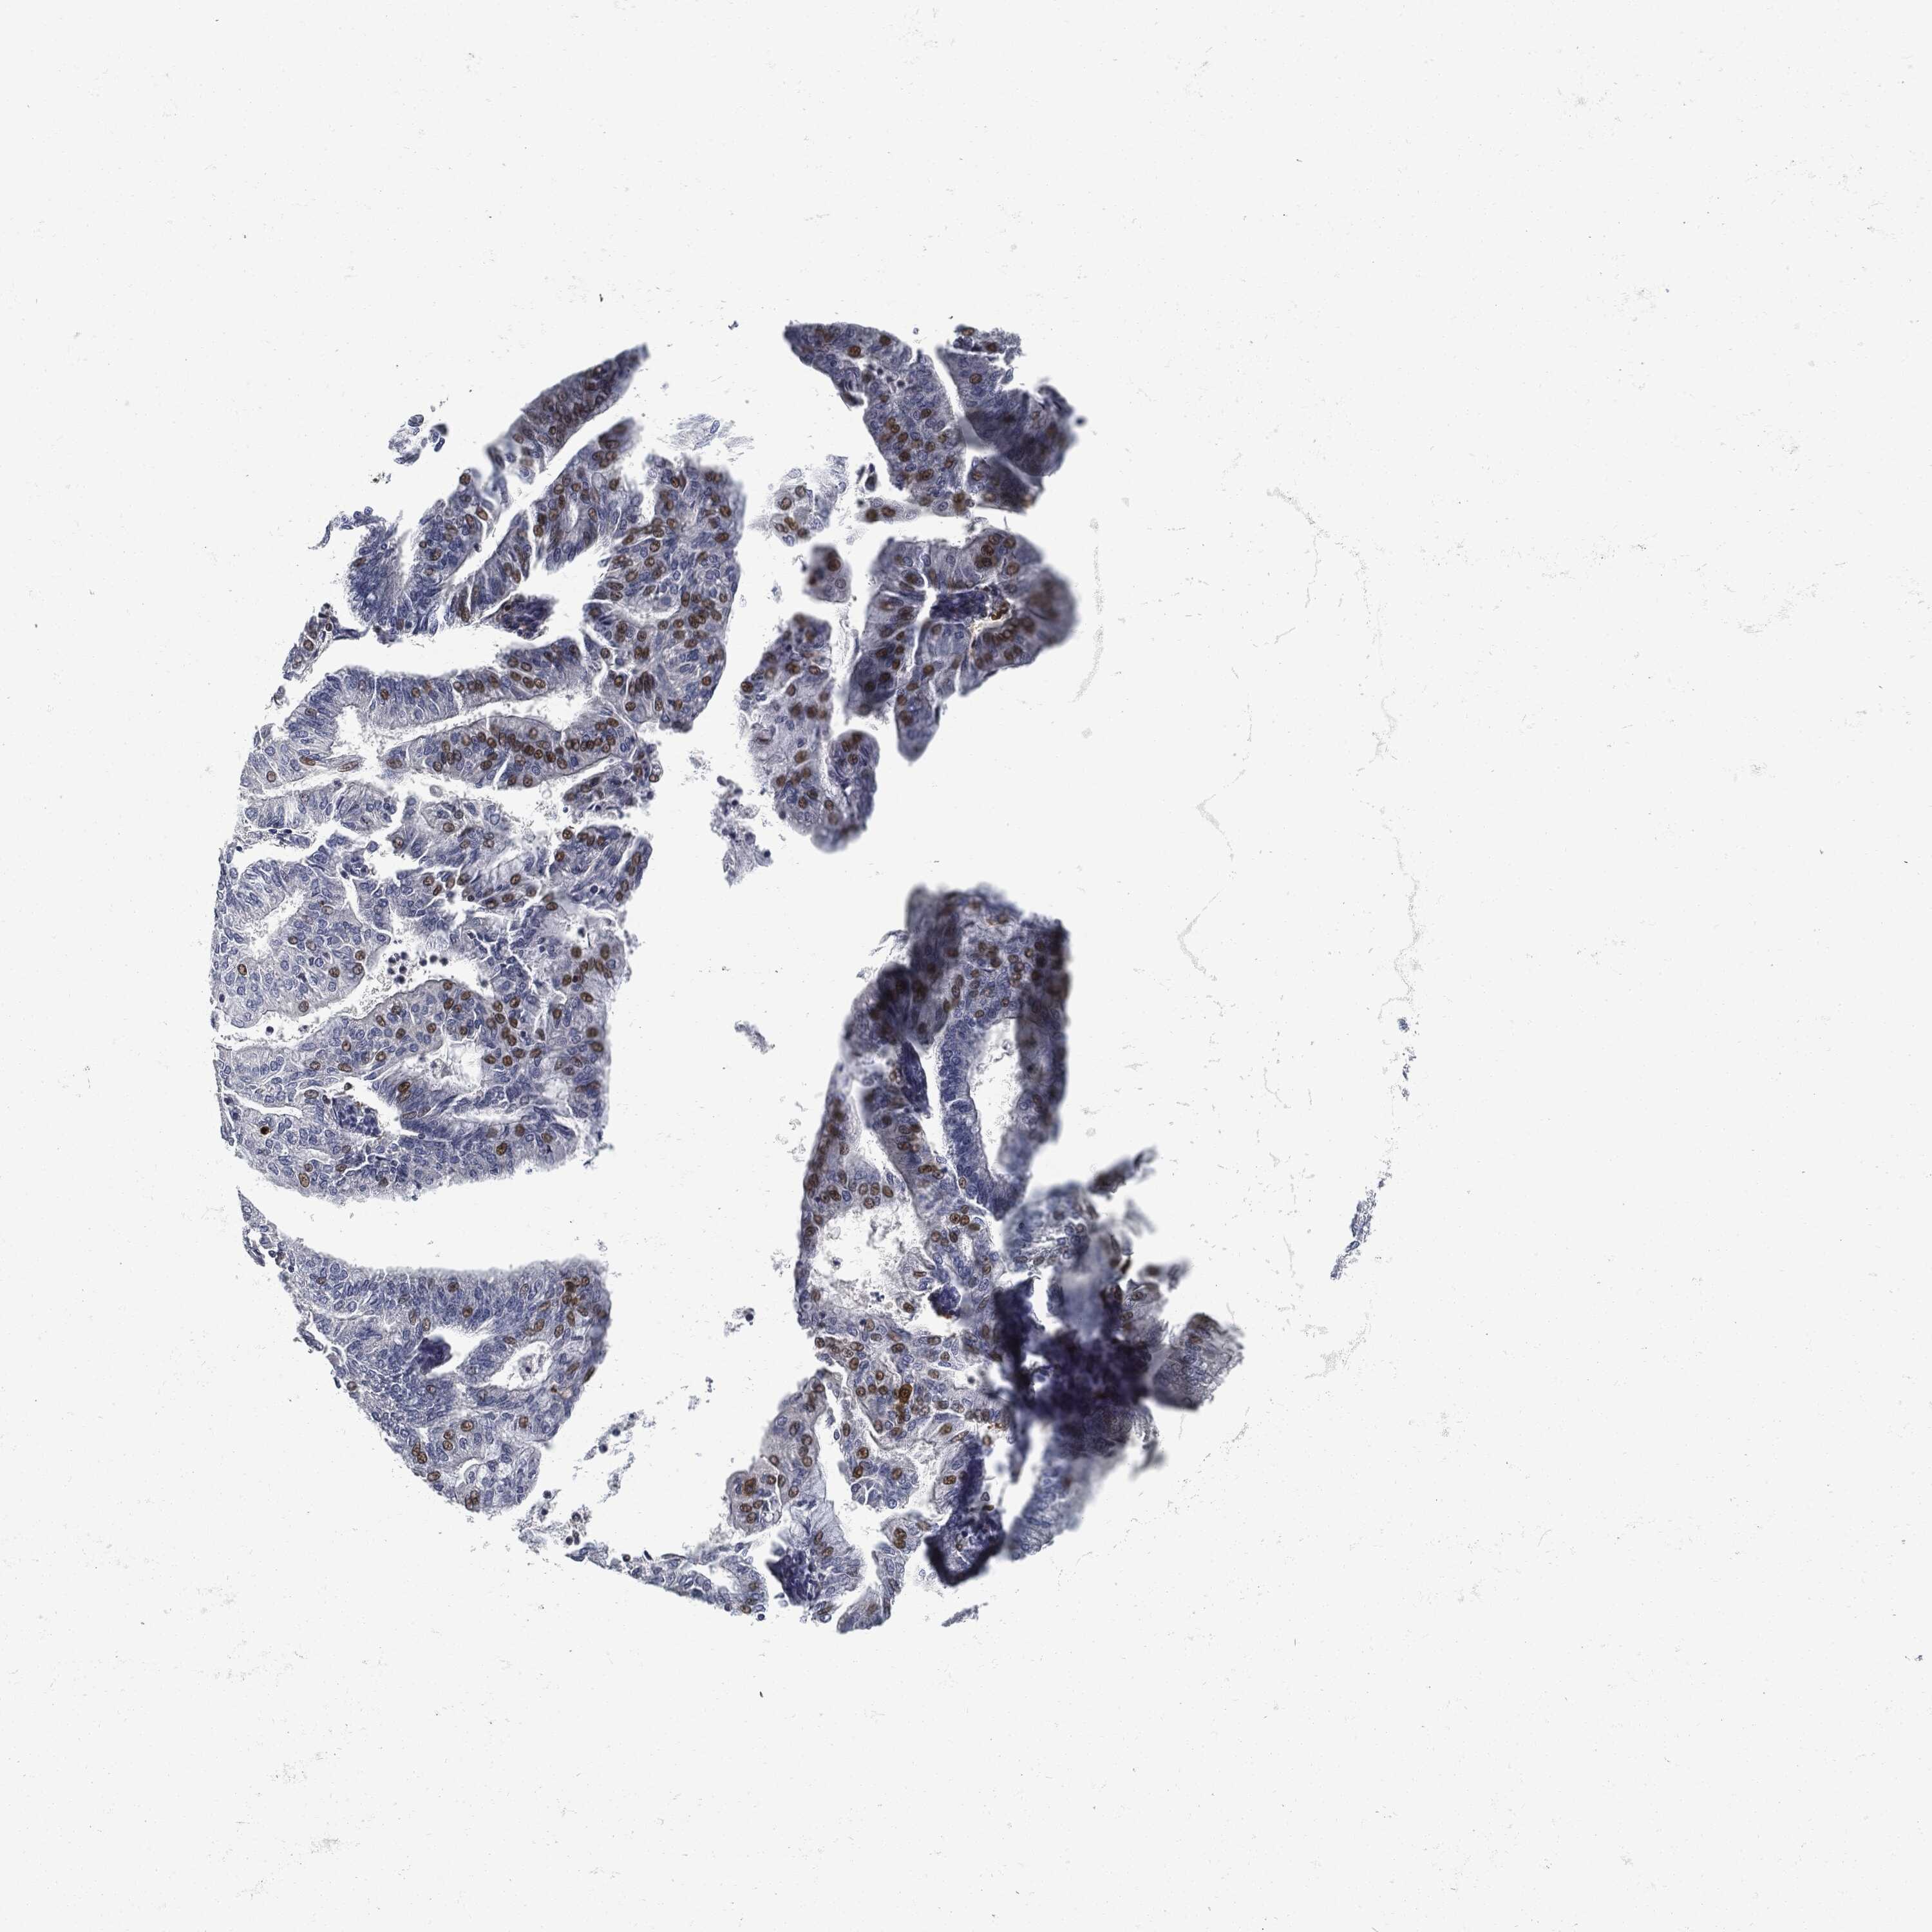

ENDOMETRIAL CANCER - Protein expressioni

A mouse-over function shows sample information and annotation data. Click on an image to view it in a full screen mode. Samples can be filtered based on level of antibody staining by selecting one or several of the following categories: high, medium, low and not detected. The assay and annotation is described here.

Note that samples used for immunohistochemistry by the Human Protein Atlas do not correspond to samples in the TCGA dataset.

Antibody stainingi

Antibody staining in the annotated cell types in the current human tissue is reported as not detected, low, medium, or high, based on conventional immunohistochemistry profiling in selected tissues. This score is based on the combination of the staining intensity and fraction of stained cells.

Each image is clickable and will lead to virtual microscopy that enables deeper exploration of all samples and also displays staining intensity scores, fraction scores and subcellular localization as well as patient and tissue information for each sample.

Antibody CAB076385

Antibody CAB080537

Staining

High

Medium

Low

Not detected

Intensity

Strong

Moderate

Weak

Negative

Quantity

>75%

75%-25%

<25%

None

Location

Nuclear

Cytoplasmic/membranous

Cytoplasmic/membranous,nuclear

Adenocarcinoma, NOS